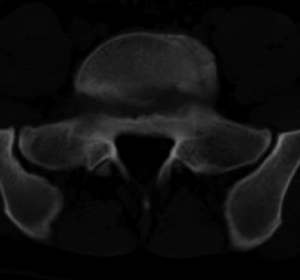

男,20,士兵,腰痛3年多,无外伤史

都是同一幅图啊,椎体内椎间盘突出。

支持!并多个椎体形成:“许莫氏”结节!

考虑:1、多发许莫尔氏结节形成;

2、建议平行腰5椎体扫描或冠矢状曲面重建除外椎弓峡部断裂。

倒数7~9幅图像示椎体后缘双边征及双关节征,支持l5轻度滑脱。

1、多发许莫尔氏结节形成;

2、椎弓峡部断裂。

3、l5轻度滑脱。

1、多发许莫氏结节。

2、腰5双侧椎弓峡部崩裂并i度前滑脱,楼主椎间盘扫描角度有问题,另外需要反倾角扫描腰5椎弓峡部。

2、腰5双侧椎弓峡部崩裂并i度前滑脱。